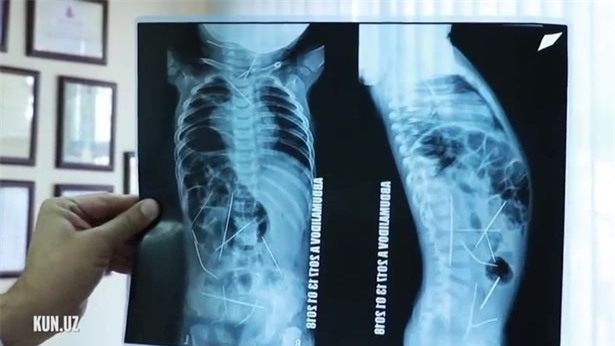

Các bác sĩ ở Uzbekistan vừa phẫu thuật rút 16 cây kim trong người một đứa trẻ 11 tháng tuổi sau khi mẹ của bé đưa đến bệnh viện vì sốt cao và khó khăn khi đi vệ sinh. Ban đầu, các bác sĩ và y tá cho rằng em bé bị viêm phổi, nhưng hình chụp X-quang cho thấy có rất nhiều cây kim nằm trong tim, bàng quang, đại tràng, cột sống và cổ.

Hình chụp X-quang cho thấy có rất nhiều cây kim nằm trong tim, bàng quang, đại tràng, cột sống và cổ của đứa trẻ. (Ảnh: Internet)

Theo thông tin từ truyền thông địa phương, các bác sĩ tại trung tâm cấp cứu tại thành phố Tashkent (Uzbekistan) đã thực hiện một cuộc phẫu thuật kéo dài 9 tiếng để loại bỏ phần lớn cây kim trong người đứa trẻ, trong đó có 9 lỗ ở bụng và 1 lỗ ở cổ, đặc biệt là đã loại bỏ được 3 kim trong tim đứa trẻ, tổng cộng có 13 cây kim được loại bỏ trong tổng số 16 cây kim. Các bác sĩ cho biết, 3 cây kim còn lại vẫn còn nằm ở những vị trí nguy hiểm nên họ chưa thế tiến hành phẫu thuật, nhưng sẽ sớm được loại bỏ theo đúng tiến độ.